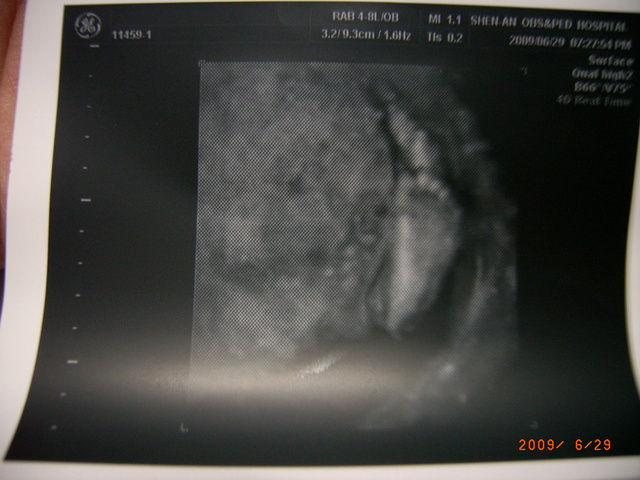

Baby的小丫…很清楚…有五指…

是四肢…右手住…左是因角度的…照出…

手都很健全…都有五指…粉可吧…